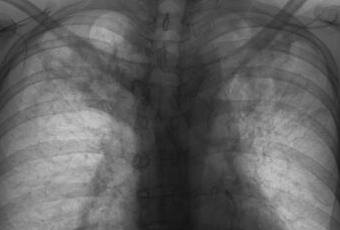

PA DE TORAX (TELE DE TORAX)

LA PROYECCION RADIOLOGICA OBTENIDA NOS MUESTRA LOS SIGUIENTES HALLAZGOS:

-Tejidos blandos, con densidad conservada, simétricos, sin evidencia de alteraciones.

-Estructuras óseas, sin evidencia de lesiones líticas, blásticas o perdida de la contigüidad. Se observa convexidad derecha de columna dorsal. Existen osteofitos marginales.

-Vía aérea permeable, tráquea con leve desplazamiento hacia la derecha por botón aórtico.

-Mediastino, con ensanchamiento de su porción superior por arco aórtico y aorta descendente.

-Corazón, con índice cardiotorácico menor a 0.5.

-Hilios pulmonares, y pulmonar izquierdo oculto.

-Trama bronco-vascular, conservada.

-Campos pulmonares, con patrón retículo nodular difuso, así como presencia de áreas en vidrio esmerilado en lóbulos superiores de ambos pulmones, con bronquiectasia en pulmón derecho.

-Recesos cardiofrénicos y costofrénicos libres.

OPINIÓN RADIOLÓGICA:

EN EL PRESENTE ESTUDIO RADIOGRÁFICO, CON DATOS DE NEUMOPATÍA CRÓNICA INTERSTICIAL (ENFERMEDAD GRANULOMATOSA), BRONQUIECTASIA EN LÓBULO PULMONAR DERECHO Y ÁREAS DE CONSOLIDACIÓN EN AMBOS LÓBULOS SUPERIORES.

CORRELACIONAR CON DATOS E HISTORIA CLINICA DEL PACIENTE